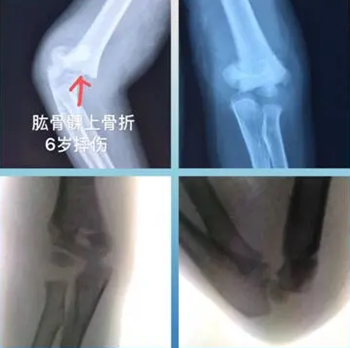

病例二:患儿男,6岁,骑自行车摔伤

图 5 术前患肢明显肿胀、畸形

图 6 术前术中对比

图 7 钢针固定、完美复位